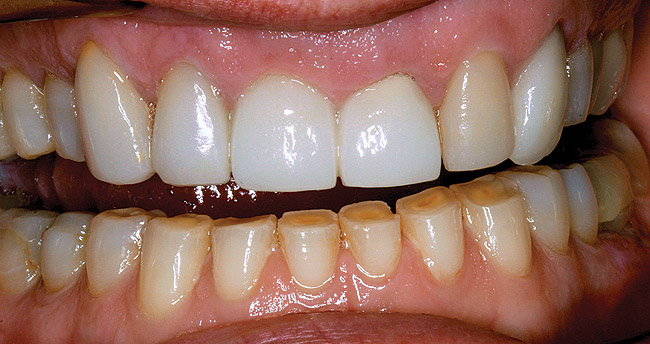

Figure 12  Adhesive dentistry with resin-based composite.

Figure 12

Figure  13   This patient was unhappy with the unesthetic appearance due to tooth surface loss.

Figure 13